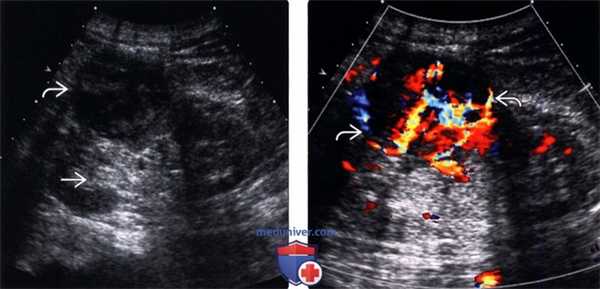

(Левый) На продольном ультразвуковом срезе визуализируется экзофитный гетерогенный светлоклеточный рак почки с задним акустическим усилением от кистозного/некротического содержимого.

(Правый) На УЗ срезе с цветовой допплерографией у этого же пациента с экзофитным гетерогенным раком почки визуализируется выраженный внутренний и периферический цветовой поток.